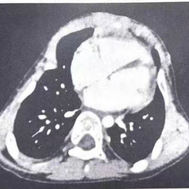

ATD can be classified into two types. Type I ATD is characterized by overall narrowing of the thoracic cage, with both the transverse and anteroposterior diameters markedly reduced compared with a normal chest. Type II ATD is a distinct form of thoracic narrowing, primarily characterized by extensive bilateral depressions of the lateral chest walls. The depressions involve multiple ribs and often extend to the costal arches.

The constriction of the chest severely impairs respiratory function, making ATD a critical condition. Most patients succumb to hypoxia soon after birth.